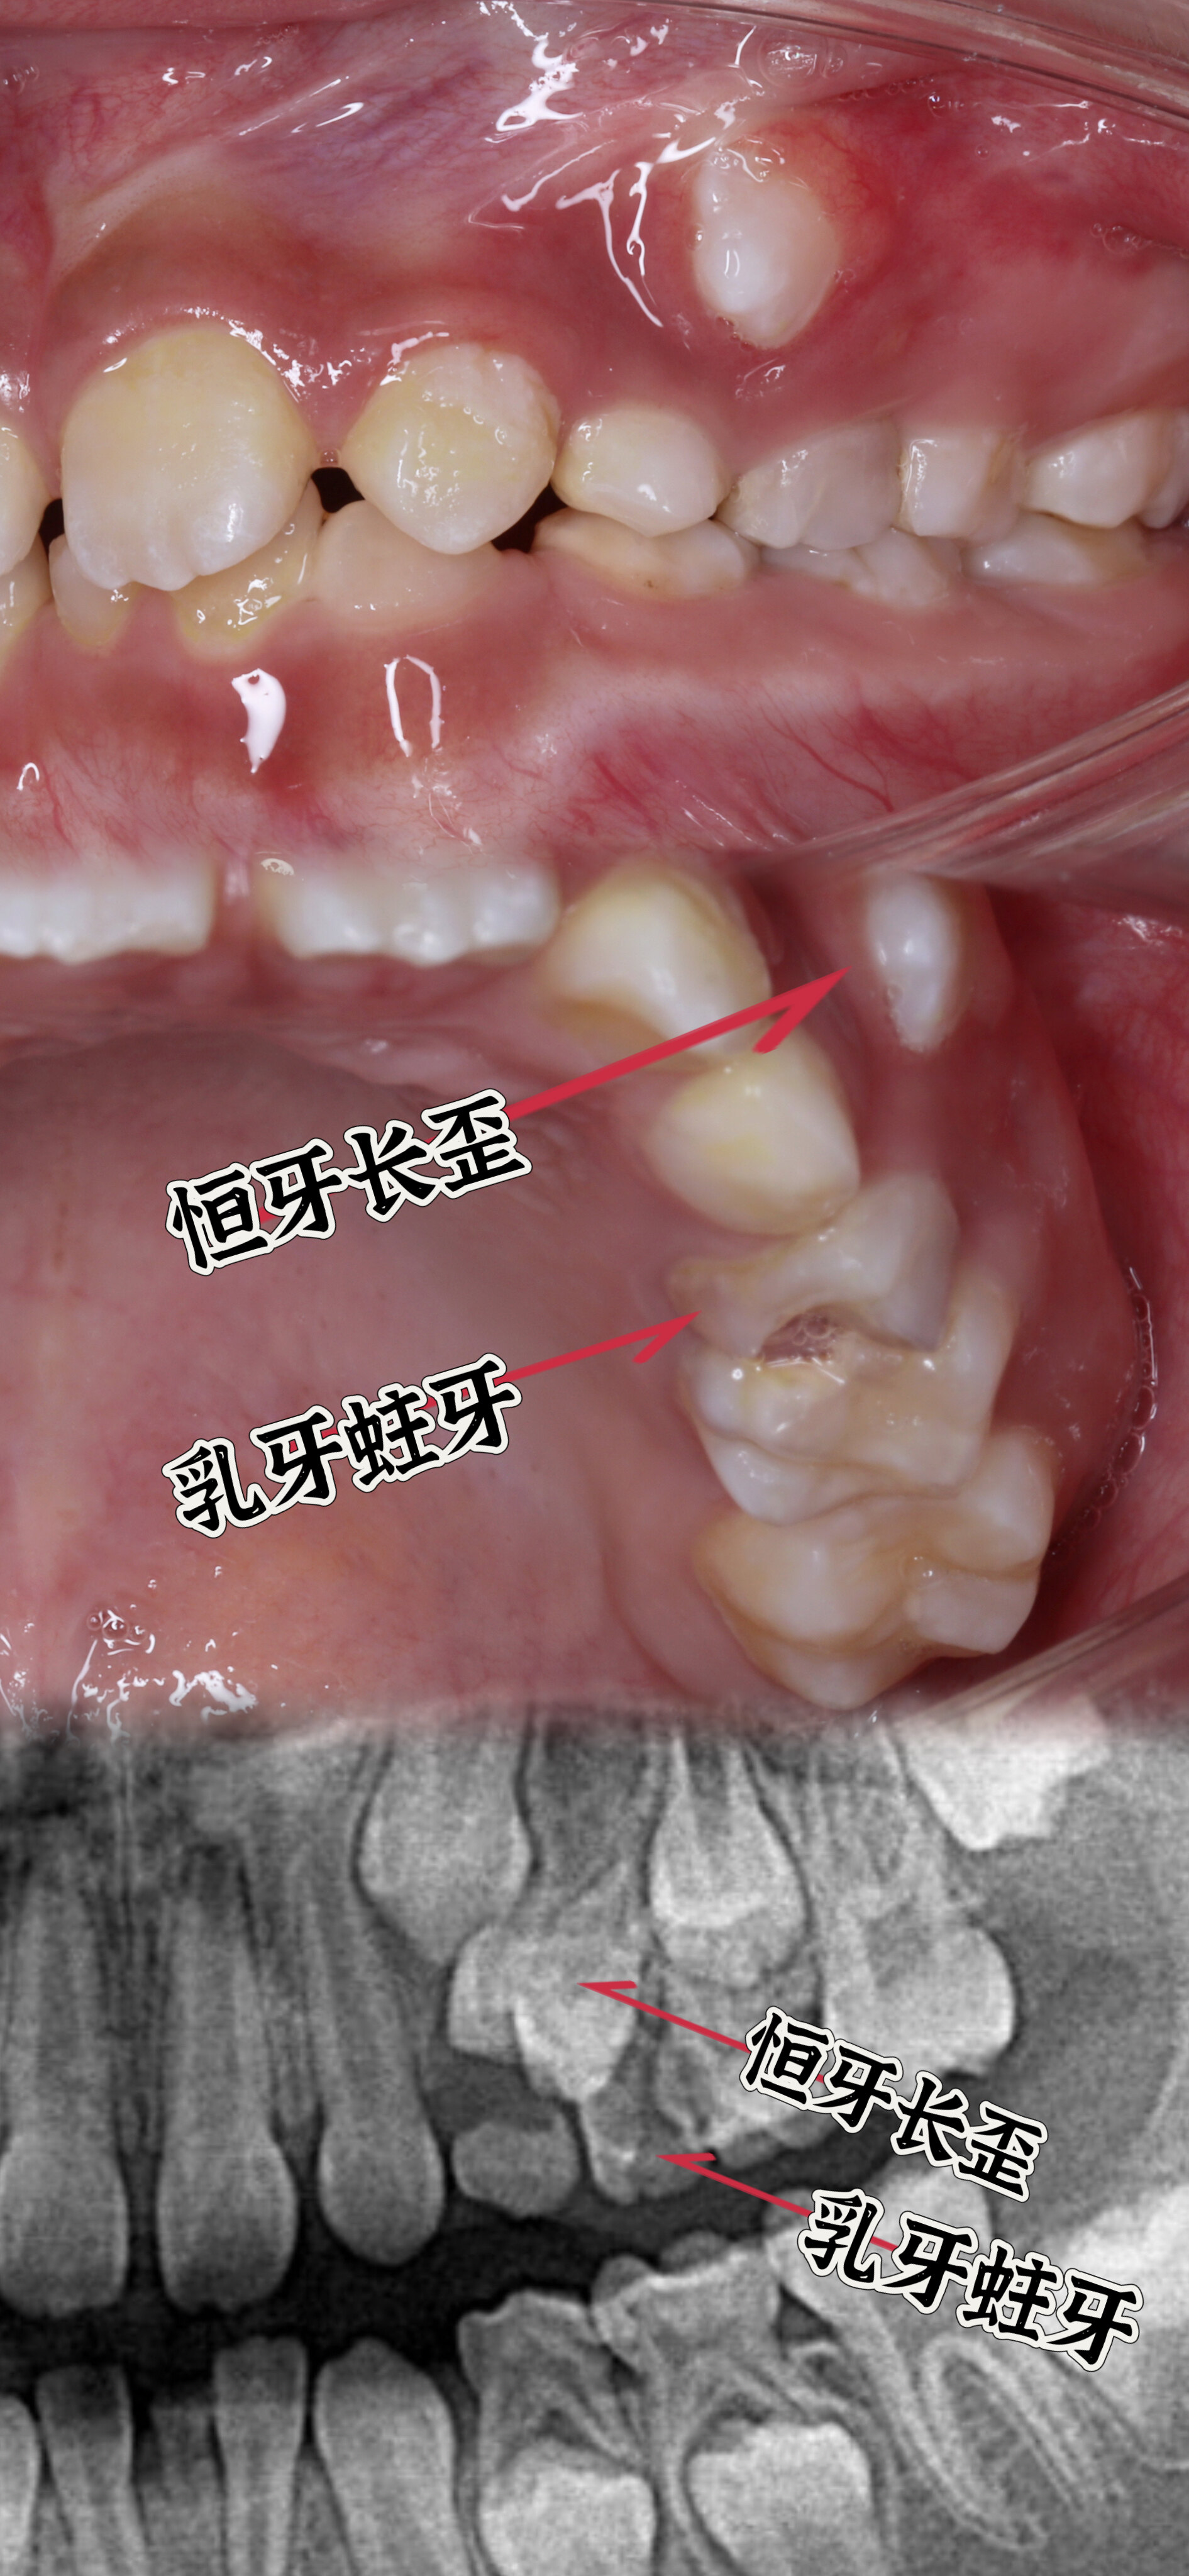

看了這張圖,還敢說乳牙蛀牙不用補?

有老觀點認為“乳牙蛀了不用補,等著換牙就好了",殊不知嚴重的乳牙蛀牙也會影響恒牙。兒童齲齒預防大于治療,家長們要注意孩子的口腔衛(wèi)生,每天2-3次刷牙,每次2分鐘,6周歲以下的兒童需要家長幫忙刷牙。兒童需每3個月或6個月到口腔科做全面檢查,及時做涂氟,窩溝封閉等預防齲齒。